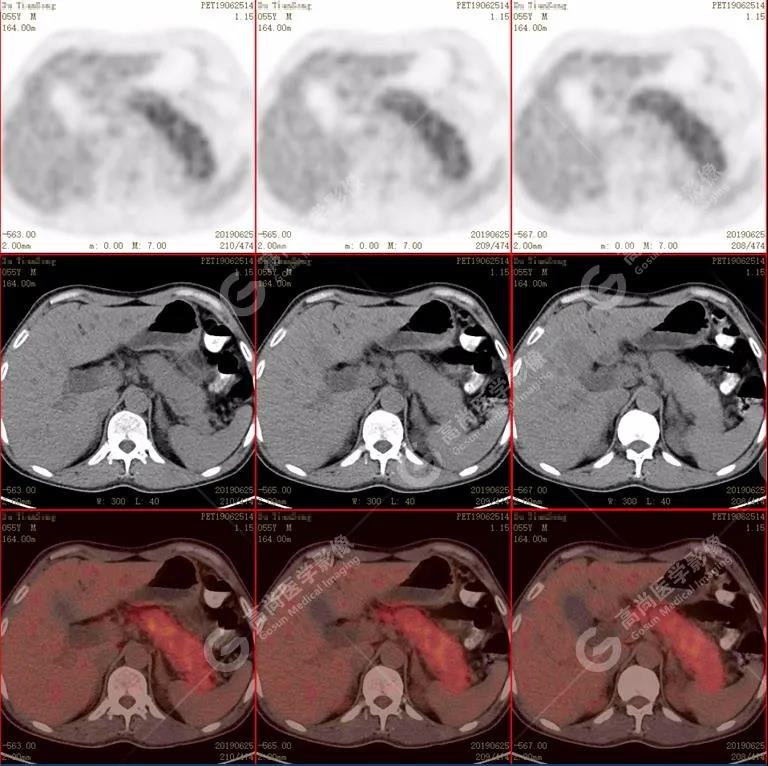

胰腺腫脹、密度均勻,代謝彌漫性不均勻增高,SUV最大值5.2  平均值4.0

(1)胰腺輕度腫脹,胰腺體尾部胰管狹窄,未見(jiàn)明顯占位性病變,代謝彌漫性增高。

?CT:胰腺體積不同程度彌漫性腫大,密度減低或正常,增強(qiáng)掃描動(dòng)脈早期強(qiáng)化低于正常胰腺,延遲期均勻一致強(qiáng)化。胰周脂肪間隙多數(shù)清晰,少數(shù)可見(jiàn)少量條狀異常密度或信號(hào)(輕度炎性反應(yīng))。